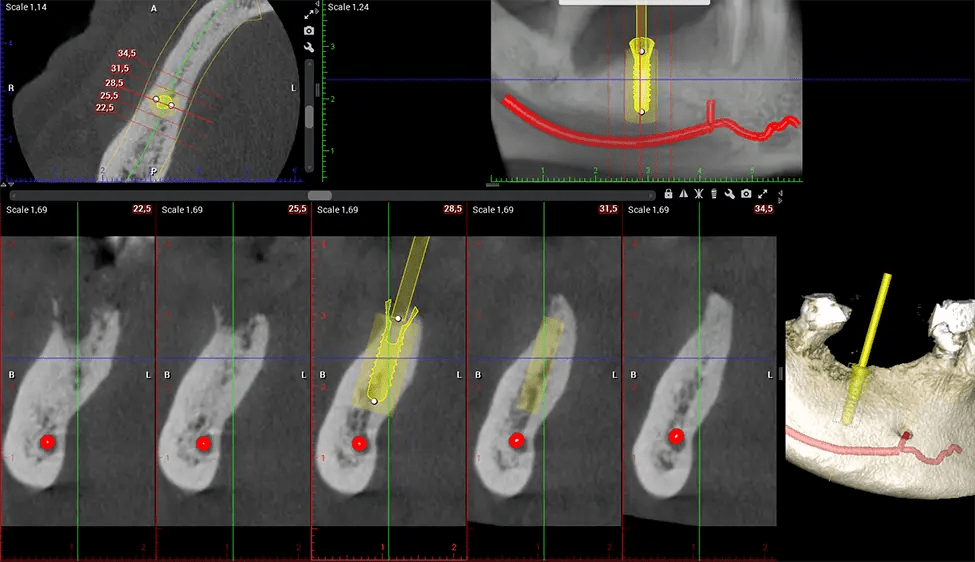

When paired with extractions, dental implant placement, or bone grafting, CBCT technology can provide you with a quicker and much more comfortable experience. This is because the 3D image provides a more detailed picture of your entire oral cavity, allowing your dentist to walk you through each step of the process before it occurs. This often helps patients feel more prepared and comfortable overall, especially if they have had a traumatic experience with past dental treatments.

The patient is first positioned in the CBCT scanner, which typically consists of a rotating arm that houses the X-ray source and a detector. The patient’s head is immobilized to ensure accurate image capture. The X-ray source and detector rotate around the patient’s head, capturing various X-ray images from multiple angles. As the X-ray source rotates, it emits the cone-shaped X-ray beam towards the detector. The detector captures the X-ray images, which are then processed by the CBCT software.

After the scanning process, the captured X-ray images are processed by the CBCT software, which applies algorithms to reconstruct a detailed 3D image of the scanned area. The software compiles these individual X-ray images and creates a digital 3D representation of the patient’s anatomy. The reconstructed 3D CBCT image can be viewed and analyzed by the dentist or radiologist. This image can be manipulated, rotated, and zoomed in or out to examine specific structures and evaluate the patient’s condition.